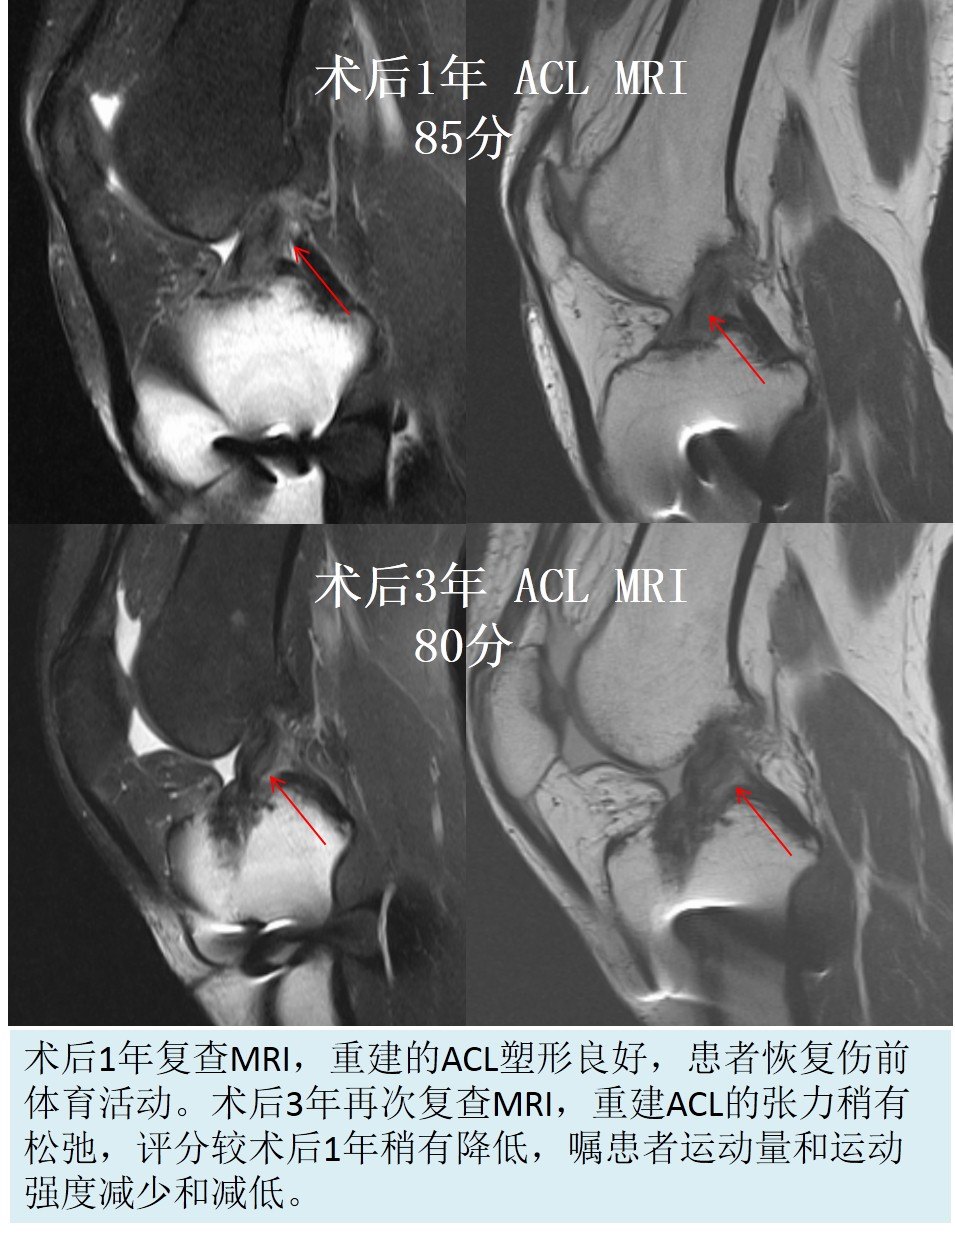

ACL重建后进行MRI评估是评估重建ACL塑形的最直观的非创伤性检查方法。我们的观点认为,如果重建的ACL在MRI上的评分在80分以上(MRI的三个评估指标,总分90分:韧带的容积-30分;韧带的张力-30分;韧带的灰度-30分),术后膝关节功能就恢复好,再次恢复到伤前运动状态的几率就大,重建韧带发生再断裂的风险就低。而且我们在随访过程能根据重建的ACL在MRI上的评分结果调整康复进程,指导患者的运动方法,以利于重建韧带的最终塑形,这个十分重要的。

前交叉韧带重建后大部分韧带在术后1-2年愈合完好,韧带塑形成熟。

有些患者在前交叉韧带重建2年后,韧带塑形完好,但是如果不加控制的进行过强的运动,韧带也会出现变化,甚至变差!